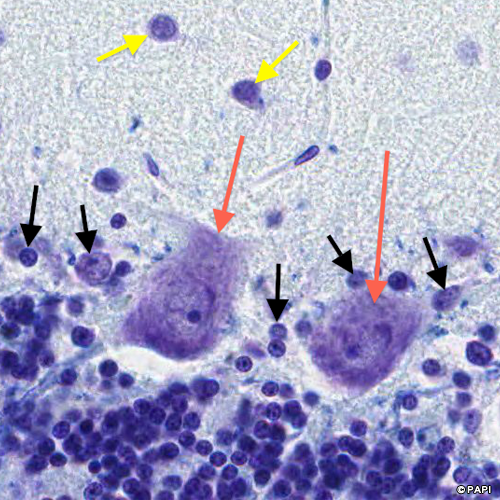

Red arrows indicate the Purkinje cells. Black arrows indicate the nuclei of the Bergmann glia which is the astrocyte in the Purkinje cell layer. Yellow arrows points the basket cell in the molecular layer.

The Purkinje cell (a yellow arrow) is surrounded by the axon (white arrows) of the basket cell (a blue arrow).